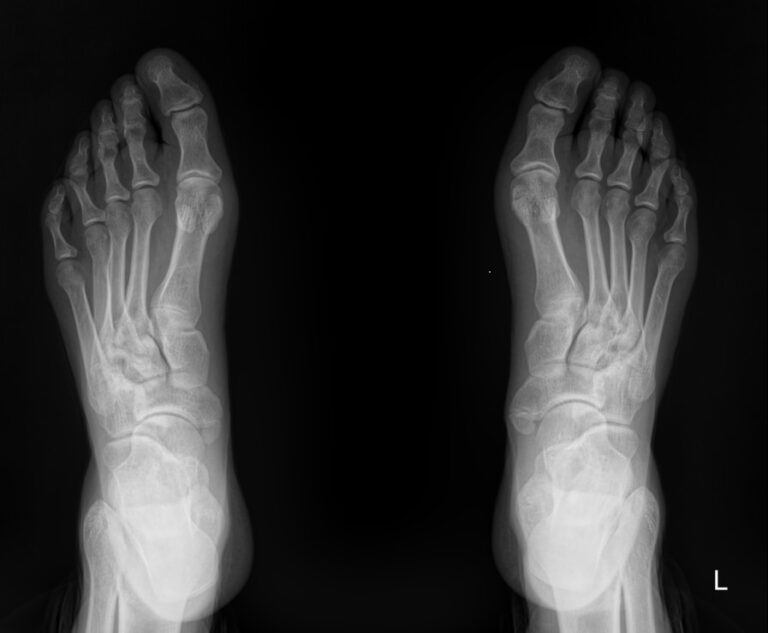

На снимке обеих стоп можно будет сравнить изменения, произошедшие в каждой стопе:

• В состоянии суставных щелей и соответствии суставных поверхностей друг другу;

• В состоянии костной ткани и надкостницы и их целостности;

• В мягких тканях.

Также указываются обнаруженные новообразования, их местоположение.